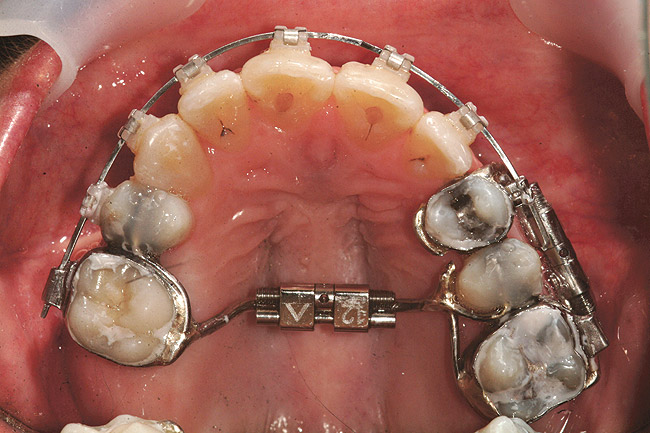

Fig 4. Note gingival inflammation caused by biologic width violation. Provisional restorations were placed on Nos. 6, 8, 9, and 11, and corticotomies were performed from Nos. 3 to 14.

Figure 4

When using SFOT, orthodontists will have to modify some of their traditional approaches depending on the type of alveolar problem. If the discrepancies are primarily dentoalveolar (such as severe crowding with alveolar bone deficiency), corticotomy surgery typically is performed within 2 weeks of orthodontic appliances placement (Figure 4 and Figure 10). This early surgery appears to maximize the alveolar correction and minimize the negative compromises from cell-mediated tooth movement alone in a deficient alveolus.